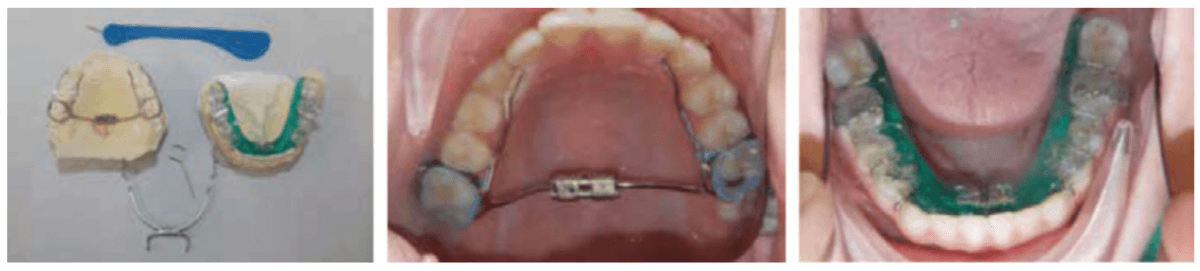

When used on mixed dentition, there will be a need to place extra buccal retention on the lower deciduous molars for the “C” clasps (Figures 12 and 13).

The evolution of printed biofriendly materials produced by Diamond Orthotic Lab for removable orthopedic development and facial pain has greatly improved treatment (Figures 14 and 15). These appliances are made of Type 12 nylon and are thermally active, making them easy to adjust with either hot or cold water.